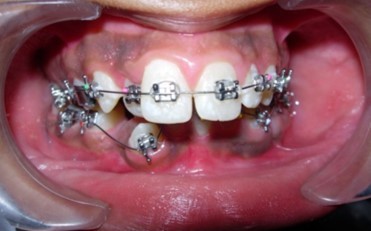

Initial alignment was done with upper and lower 0.014-inch nickel titanium archwires (Figure 6a,Figure 6b,Figure 6c). This was followed with 0.016-inch nickel titanium archwires. Space for blocked out 42 was created by an open coil spring on a 0.018-inch stainless steel archwire. Deep bite was corrected with a lower 0.016-inch reverse curve nickel titanium wire. Extraction spaces in the maxillary and mandibular dental arches were closed with 9mm nickel titanium retraction coil springs attached to crimpable hooks on 0.017 x 0.025-inch stainless steel archwires and finishing and detailing was completed with 0.019 x 0.025-inch stainless steel archwires.

Figure 6a.Initial levelling and alignment – Upper / Lower 0.014-inch nickel titanium wires – Frontal

Figure 6b.Initial levelling and alignment – Upper / Lower 0.014-inch nickel titanium wires – Right

Figure 6c.Initial levelling and alignment – Upper / Lower 0.014-inch nickel titanium wires – Left